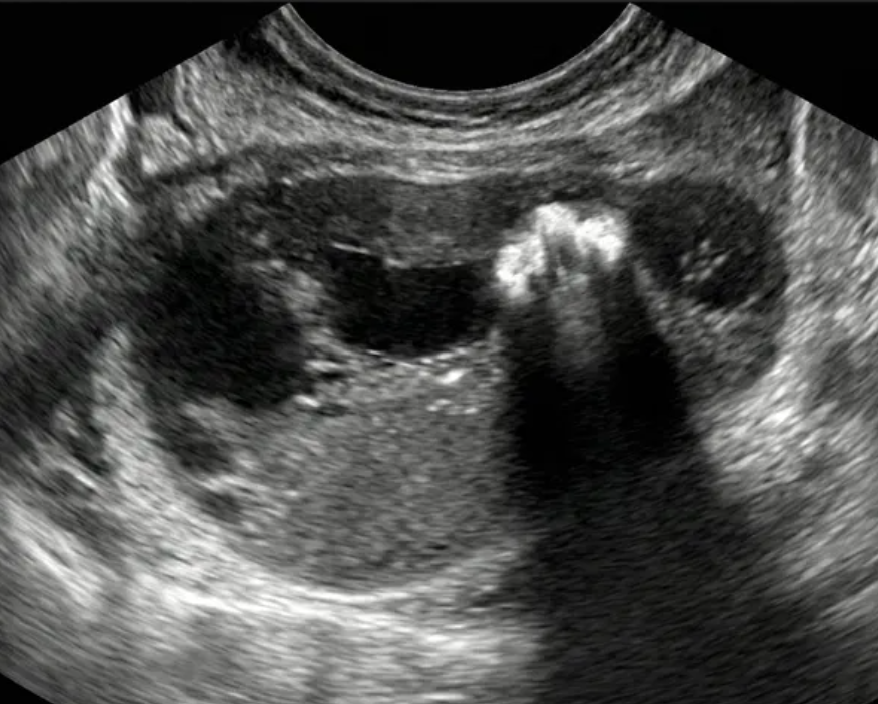

As regras simples do IOTA são um sistema de classificação baseado em características ultrassonográficas específicas que ajudam a distinguir massas anexiais benignas de malignas.

Classificação Benigna: Quando apenas regras benignas estão presentes (uma ou mais).

Classificação Maligna: Quando apenas regras malignas estão presentes (uma ou mais).

Classificação Indeterminada: Quando nenhuma regra está presente, ou quando há presença simultânea de regras benignas e malignas.